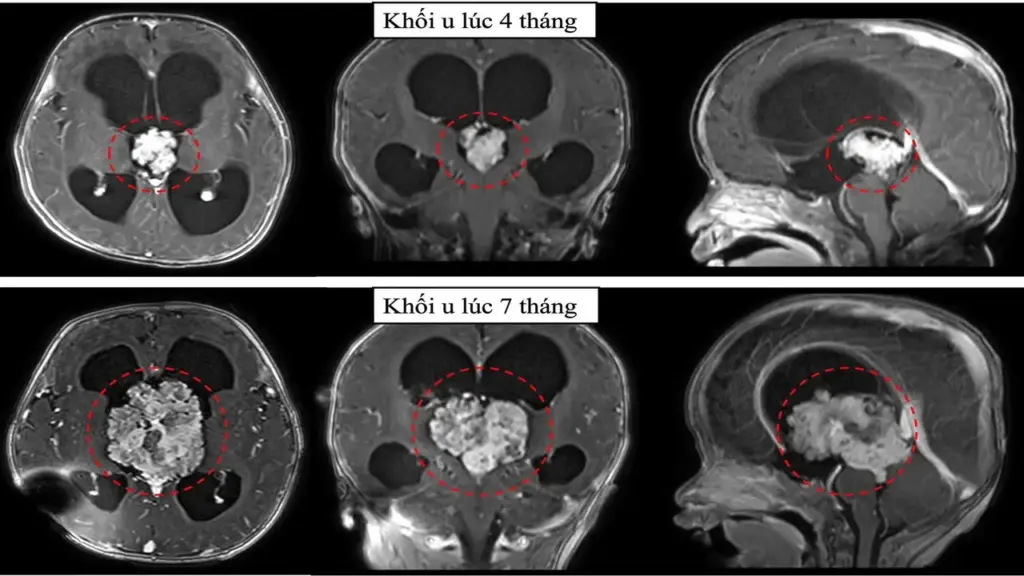

Quá trình thăm khám, bác sĩ ghi nhận bé có tình trạng tăng áp lực nội sọ, ảnh siêu âm cho thấy khối u chèn ép vùng não thất III, gây giãn não thất nặng. Tiếp tục chụp cộng hưởng từ sọ não, bệnh nhi được xác định tình trạng não úng thuỷ tắc nghẽn, với khối u nằm ở vị trí có nhiều cấu trúc thần kinh quan trọng xung quanh.

Kết quả giải phẫu bệnh xác định, bệnh nhi mang u đám rối mạch mạc không điển hình độ 2, một khối u hiếm gặp của hệ thần kinh trung ương.

Nhưng 3 tháng sau, khi chụp phim cộng hưởng từ sọ não, bác sĩ phát hiện khối u tăng kích thước hơn gấp 3 lần. Không thể trì hoãn thêm, ê-kíp điều trị tư vấn gia đình việc phẫu thuật mổ lấy u để cấp cứu cháu bé.

TS.BS Trần Minh Huy, khoa Ngoại Thần kinh, chia sẻ, đây là ca mổ rất khó khăn, khi khối u kích thước lớn (6cm), tăng sinh mạch máu nuôi và phát triển trong lòng não thất. Ngoài ra, với thời gian cuộc mổ kéo dài, nguy cơ mất máu nhiều trên bệnh nhi 7 tháng tuổi đòi hỏi năng lực chuyên môn và phối hợp liên chuyên khoa chặt chẽ.